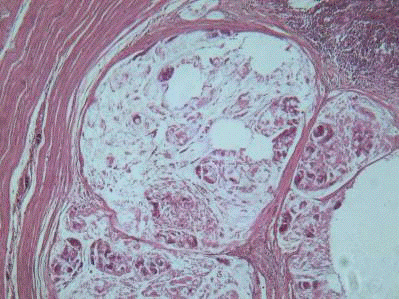

Гистологический срез. Опухоль представлена крупными железами, в которых

располагаются сосочки и слизь. Эпителий довольно хорошо дифференцирован и

занимает примерно 55% площади среза.